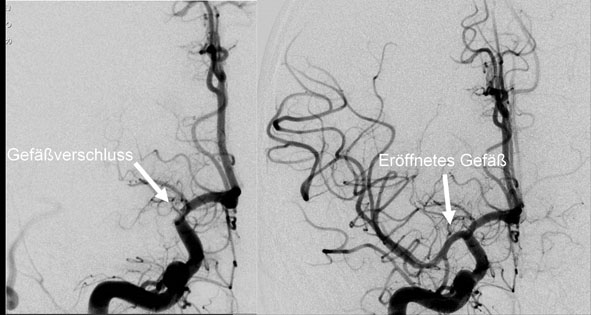

• Neurothrombektomie (Stroke-/Schlaganfalltherapie)

• Carotis-Stents und aller Kopf-Hals-Gefäße